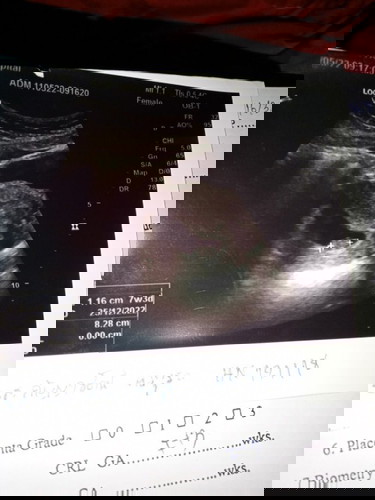

อัลตราซาวด์ตอน7สัปดาห์3วัน แบบนี้ปกติไหมค่ะ. ท้องแรกค่ะ❤️👶

ปกติค่ะแม่ บ้านนี้เห็นตอน 7 วีคค่ะ